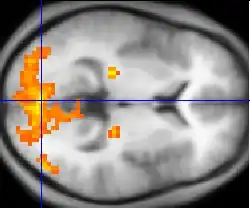

Desde la década de 1980 fueron desarrollados sofisticados procedimientos de neuroimaginería como el fMRI (Imágenes de resonancia magnética funcional), para incrementar el conocimiento acerca de las funciones cerebrales.

Neuroimagenería: CAT, MRI, fMRI, PET, SPECT, DOT, EROS